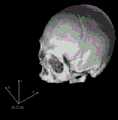

图3三维校正。Figure 3 Three-dimensional correction.

第二步:采用ITK三维刚性配准,对影像进行校正(如图3所示)。Step 2: Use ITK 3D rigid registration to correct the image (as shown in Figure 3).